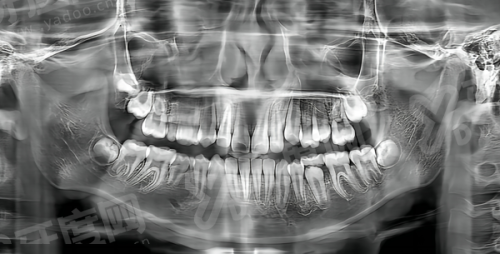

1、科室配备了一系列较为精良的口腔医疗设备,如数字化X光机、口腔综合治疗台、超声波洁牙机等,这些设备能够为诊断和治疗提供更正确的数据支持,提高治疗的精细度和成效。